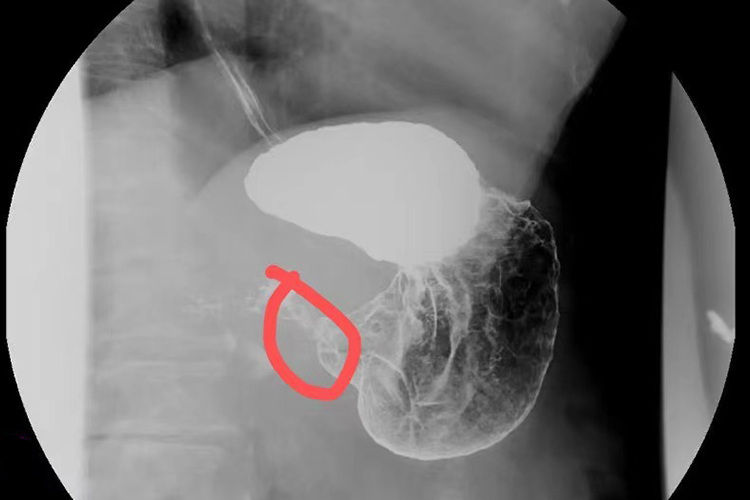

胃溃疡:其直接征象是龛影呈白色钡点或钡斑,周围黏膜皱襞呈星芒状向龛影口部集中。